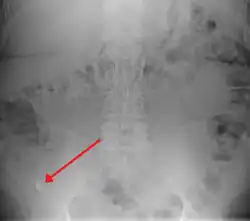

A fecalith marked by the arrow which has resulted in acute appendicitis.

A fecalith is a stone made of feces. It is a hardening of feces into lumps of varying size and may occur anywhere in the intestinal tract but is typically found in the colon. It is also called appendicolith when it occurs in the appendix and is sometimes concurrent with appendicitis.[1] They can also obstruct diverticula. It can form secondary to fecal impaction. A fecaloma is a more severe form of fecal impaction, and a hardened fecaloma may be considered a giant fecalith. The term is from the Greek líthos=stone.[2]

A small fecalith is one cause of both appendicitis and acute diverticulitis.